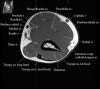

- Sagittal section

1) Biceps Brachii tendon and Brachiallis muscles

2) Radial head for radiographically occult fractures

3) Distal Triceps tendon